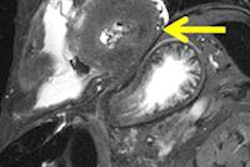

The comparison can reveal the ancestry and gender of unidentified remains using only CT data from the skull, which is particularly useful when working with incomplete skeletal remains, Ross said.

Traditionally, the size of the so-called 3D-ID database has been limited to contemporary skull data with clearly recorded demographic histories. The goal of the study was to determine if good skull coordinate data could be obtained from living people by examining CT scans; this, in turn, could produce a more robust database.